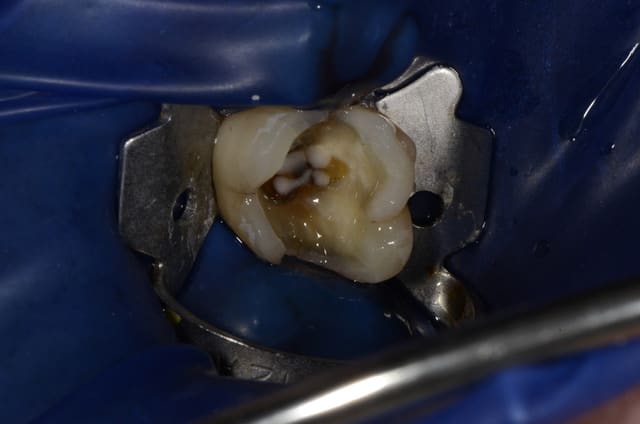

en supposant que le coté de la dent où il y a l'anneau du crampon soit le coté distal, et que, d'après l'anatomie d'une 5 qui se dessine sous la digue, le coté vestibulaire est à gauche, je parlais de la felure qui est en distal (la toute petite felure, pas les felures de la cuspide mésio vestibulaire). En relisant vos post, j'aurais effectivement dû recouvrir les cuspides vestibulaires plus largement.

voilà la photo post op, on remarquera que le joint en vestibulaire distal est un peu visible, et on peut suspecter un enfoncement incomplet de l'inlay.

Pourrions nous revenir sur cette micro felure (on la voit pas bien à cause de l'adhésif du multilink que j'avais déjà appliqué avant que je me décide à prendre la photo); à cette vue là, auriez vous décidé d'abaisser la limite DISTALE?